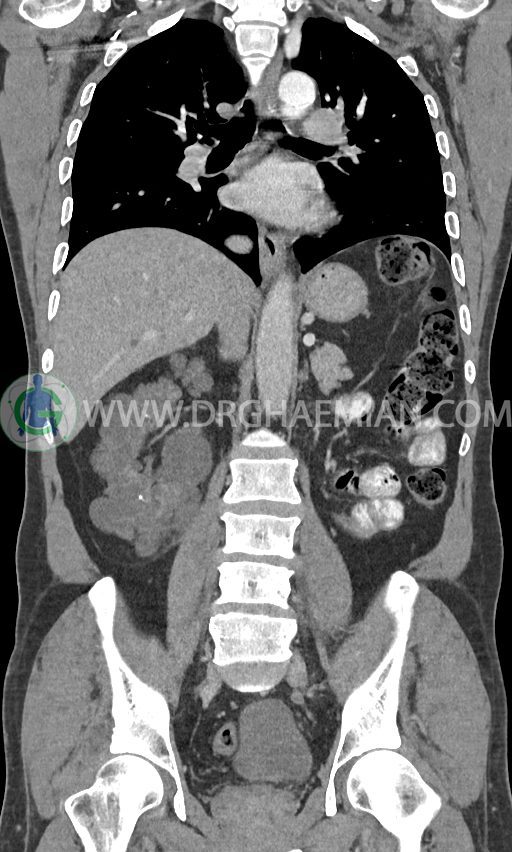

سی تی اسکن ریه، شکم و لگن با استفاده از تشعشعات تصاویر عرضی از نواحی ریه، شکم و لگن ایجاد میکند. در این کیس کلیه پلی کیستیک، کیست در کبد، پروستات بزرگ تر از نرمال، هرنی اینگوینال و … دیده می شود.

در سی تی اسکن اسپیرال ریه ، مدیاستن و شکم و لگن با کنتراست خوراکی و وریدی (مولتی دیدکتور 16 با مقاطع ظریف و بازسازی های ساژیتال و کرونال) :

کیستهای متعدد به قطر تا 10mm پراکنده در کبد

نشانه های نفرکتومی چپ

نشانه های ADPKD در کلیه راست بزرگ تر از نرمال ( 90x160mm ) ، همراه با کیستهای فراوان به قطر تا 40mm و سنگهای فراوان به قطر تا 12mm

کلیه پیوندی به ابعاد 55x70x120mm در ایلیاک فوسای چپ با enhancement طبیعی سیستم پیلوکالیسی و حالب پیوند و ترشح کنتراست به مثانه

پروستات با قطر عرضی 60mm بزرگ تر از نرمال

هرنی اینگوینال راست حاوی چربی و لوپ روده

نشانه های بزرگی قلب

کلسیفیکاسیون دیواره آئورت و شریان های ایلیاک

مشهود است.